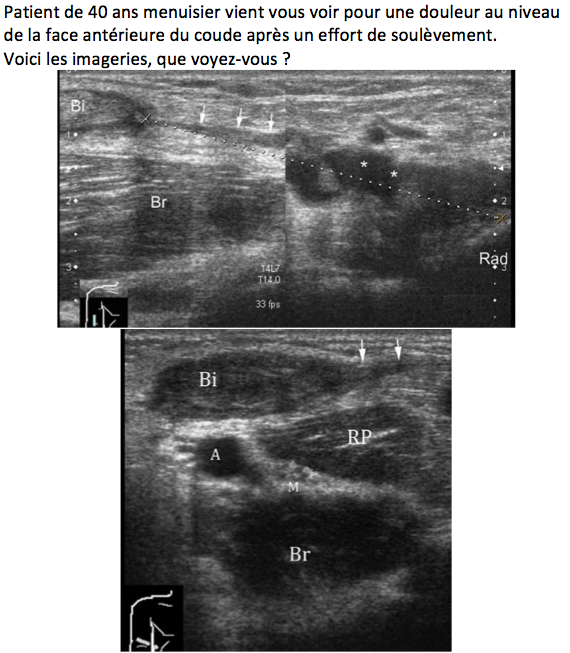

Rupture complète du tendon distal du biceps.

Coupe sagittale :

Coupe horizontale :